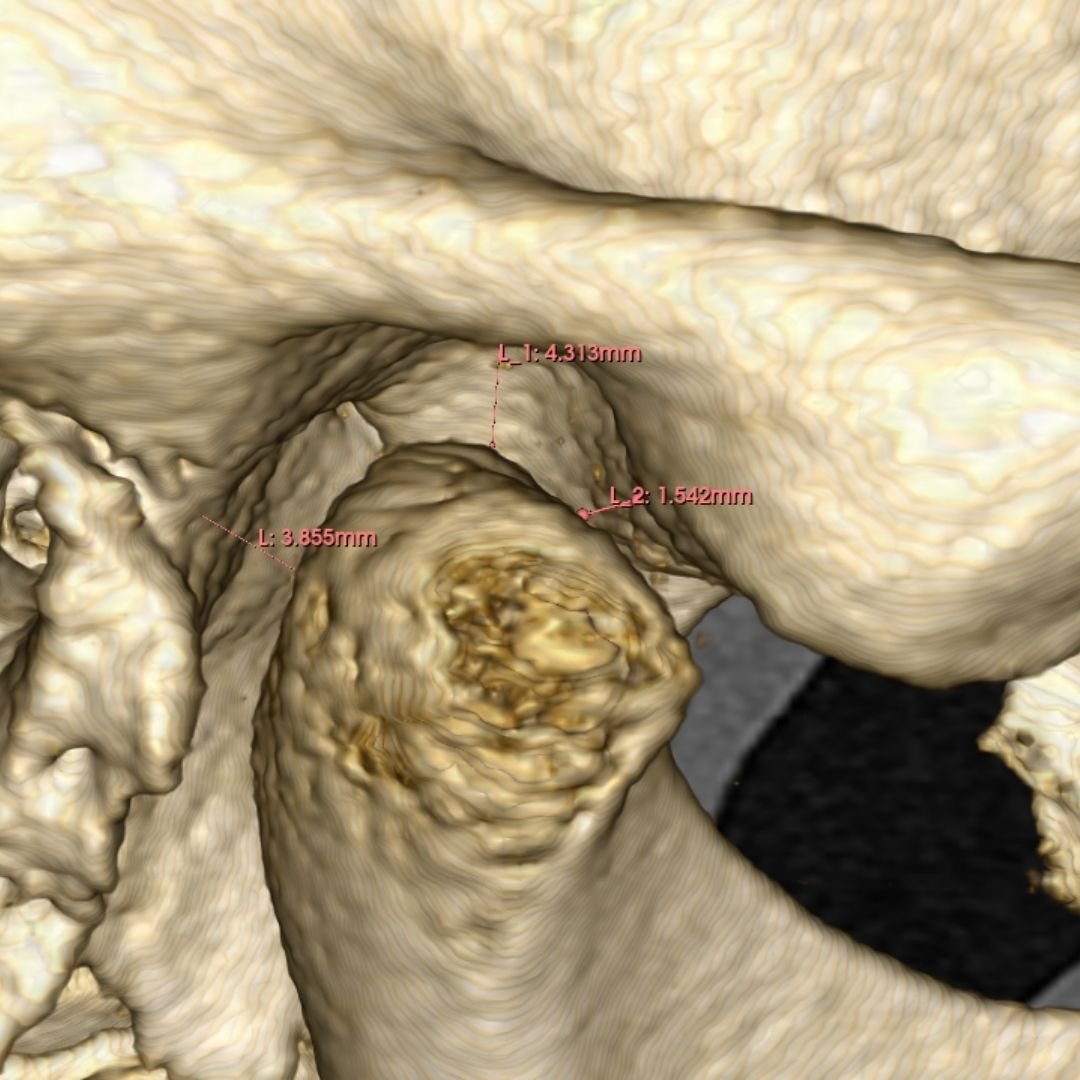

En la actualidad, la tecnología en odontología ha permitido realizar estos tratamientos de manera más eficiente y cómoda para el paciente. La técnica del Clon digital o Paciente Virtual, por ejemplo, permite obtener un modelo digital dinámico del paciente, lo que permite diseñar todo el tratamiento digitalmente y utilizar bibliotecas de dientes naturales para obtener un resultado estético y funcionalmente óptimo. Gracias a esta técnica, se pueden realizar tratamientos en menos citas y con mayor comodidad para el paciente.